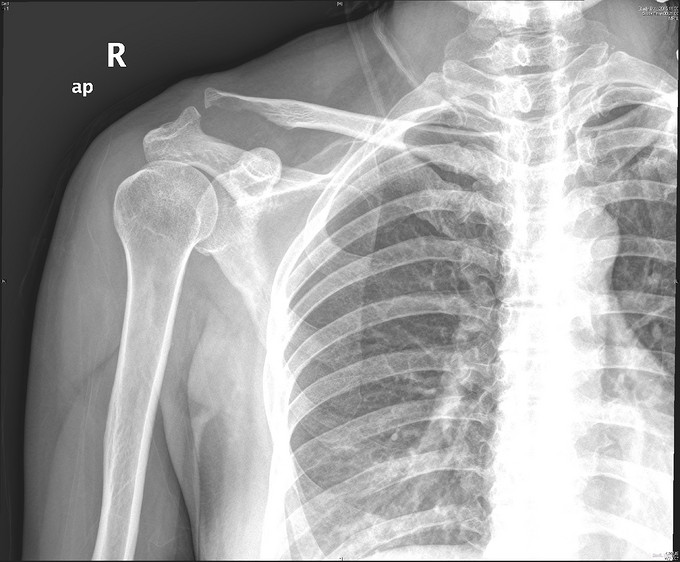

主诉:右肩疼痛5月,加重伴活动受限2月余。 现病史:患者,女性,45岁。5月前无明显诱因下出现右肩关节疼痛不适症状,偶伴有夜间痛,经休息等保守治疗后现疼痛症状略缓解。后患者至外院就诊,予口服药物等保守治疗,效果不佳,且有加重趋势。2月余前患者自觉右肩疼痛较前明显,伴活动受限。外院行MRI检查示:右肩关节内积液、右肩峰骨质增生、右肩袖肿胀、右肩盂唇信号异常。后患者来我院就诊,查右肩X线示:右肩峰前外侧见一骨性突起。门诊结合病史及体征,诊断“右肩峰下撞击综合症、右肩峰占位”收入院,行进一步治疗。

查体:右肩关节周围肌肉萎缩,右肩周压痛(+),右肩前方压痛(+),无明显肿胀。右肩关节主被动活动度明显受限,Hawking征(+),Neer征(+),Jobes征(-),Speed(+),O’brein征(-),Drop Arm(-)、熊抱试验(-)。外展肌力(Ⅳ)级。双上肢感觉正常。 辅查:见现病史,图片见下。

入院诊断:右肩峰下撞击综合症、右肩峰占位 治疗:右肩关节镜下肩峰成形,占位切除术